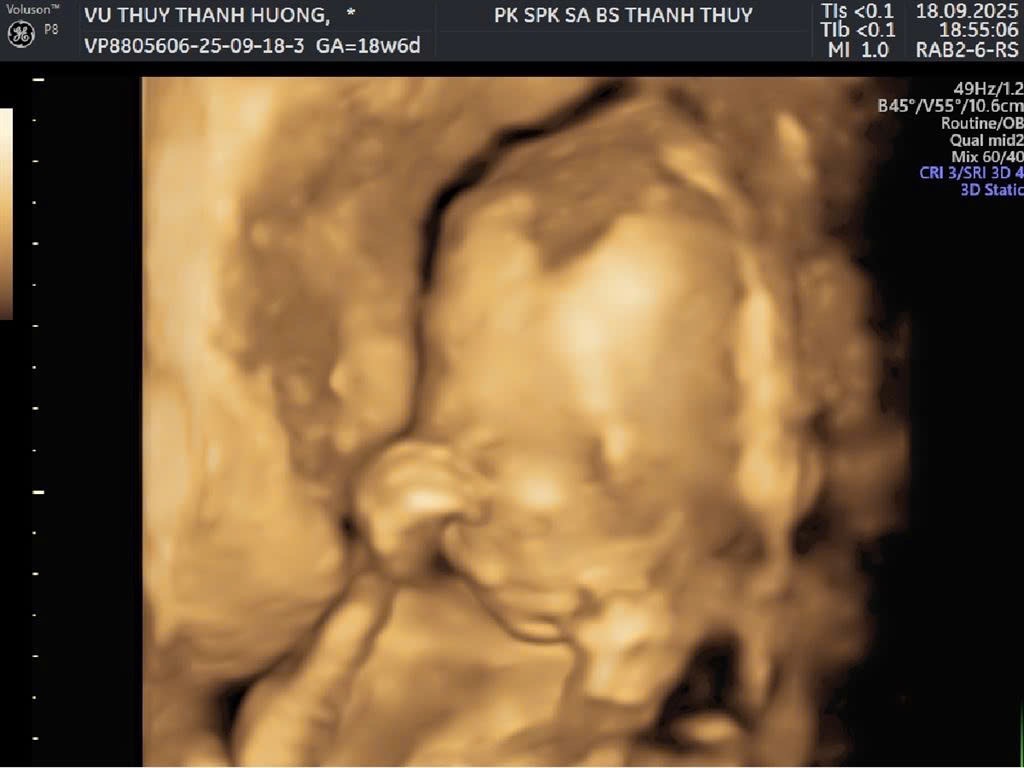

Vũ Thuỵ Thanh Hương